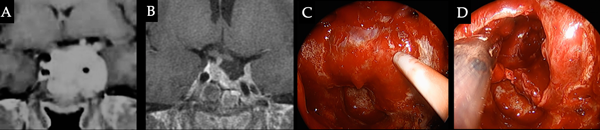

Caso 4. Apoplejía. Paciente masculino de 16 años de edad que consulta inicialmente por cefalea y alteraciones visuales, en el laboratorio presentaba PRL de 3700 ng/ml. Inició tratamiento con cabergolina, durante el cual presentó empeoramiento visual + cefalea, observándose en la RM sangrado tumoral por lo cual se decide conducta quirúrgica. La anatomía patológica informó adenoma lactotropo con Ki 67 10%. El paciente requirió AD y RT adyuvantes para control de la enfermedad. A-B. RM preoperatoria que evidencia macroadenoma con extensión supraselar y componente hemorrágico. C-D. RM post cirugía, AD y RT. E. Tumor con contenido hemático. F. Cavidad post resección tumoral parcial.